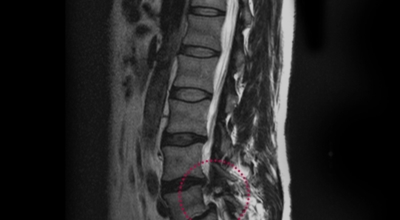

여러 개의 작은 척추뼈가 모여서 척추라는 신체의 기둥을 이루게 돼요. 척추뼈 사이에는 척추뼈끼리 부딪치는 것을 방지하는 쿠션 같은 역할을 하는 '디스크(disc)'라는 말랑말랑한 젤리 같은 구조물이 있는데 우리말로는 '추간판'이라고 합니다.

디스크(추간판)의 한가운데에는 젤리같이 찐득찐득한 '수핵'이라 하는 물질이 들어 있어요. 그 주변에 수핵을 둘러싸는 '섬유륜'이라 하는 두꺼운 막이 있는데 디스크는 전체적으로 자동차의 타이어와 같은 형태라고 합니다.

디스크는 일어선 상태에서는 중력을 받아 납작해져서 바깥쪽으로 약간 볼록한 형태가 된다고 합니다. 디스크는 그 특수한 구조 때문에 웬만한 힘이 가해져도 효율적으로 쿠션 역할을 할 수 있겠습니다. 그러나 급작스럽게 무거운 물건을 들어 올리거나, 부자연스러운 자세를 오랜 시간 취하면 디스크에 무리한 힘이 가해지면서 디스크가 밖으로 돌출이 되게 돼요. 심한 경우 디스크를 감싼 막이 터지면서 그 안에 있는 수핵이 튀어나오게 돼요.

디스크는 대개 후방이나 후외방으로 돌출되는데 이때 바로 곁에 있는 신경을 누르게 된다고 합니다. 돌출된 디스크는 척추의 어느 부위에나 일어날 수 있어요. 목에 생기면 '목 디스크', 등에 생기면 '등 디스크', 허리에 생기면 '허리 디스크'라고 부른다고 합니다.

이와 같이 디스크가 돌출되어 신경을 눌러 요통 또는 다리가 아프고 저린 증상을 유발하는 병을 '추간판 탈출증' 및 '디스크 탈출증'이라고도 불러요. 발생 빈도별로 보면 허리 디스크가 가장 흔합니다. 그다음이 목 디스크이지요. 등 디스크는 드문 병이라고 합니다.